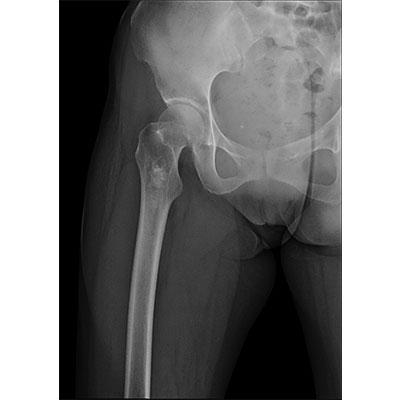

以微知形 為愛負責 微劑量 極速曝光 PLX8500E/F

● 短曝光、高熱容,拍片數量多、效率高。

● 輕松應對大型體檢中心高強度的拍片要求。

● 采用自主研發的技術,在保證優質圖像的前提下,大大降低X射線劑量,用心呵護醫護工作者及患者的健康。

● 短曝光時間,便于老年人、兒童、殘疾人進行臨床拍攝。避免這類群體因不能有效控制身體運動等因素造成的運動偽影,提高攝片質量及效率。